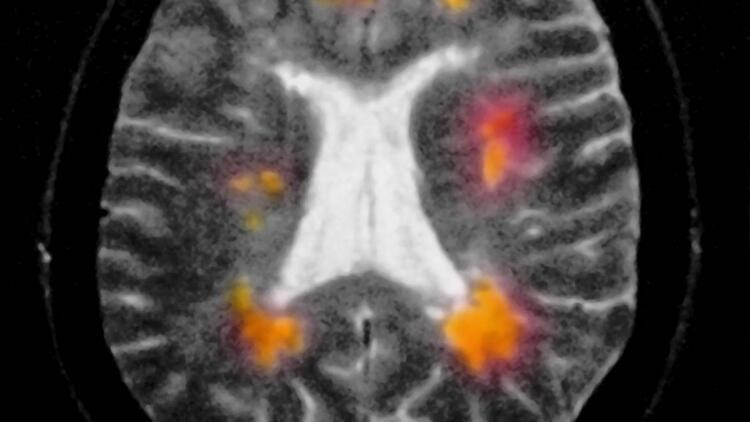

Öncelikle şunu belirtmek gerekir ki bu hastalığa "multipl" denmesinin nedeni, beyin ve omuriliğin birçok farklı alanını etkilemesindendir. Aniden ortaya çıkabilir ya da kaybolabilir. Belirtileri çok çeşitlidir. Hastadan hastaya değişiklik gösterebileceği gibi aynı hastada da zaman içinde farklılaşabilir.

"Skleroz" denmesinin nedeni ise hastalığın beyin ve omuriliğin hasarlı alanlarında sklerozan plaklar yani sertleşmiş dokular oluşturmasıdır. Özetle MS, merkezi sinir sistemini oluşturan beyin ve omurilik üzerinde yıkıcı etkileri olan, kişinin yaşamsal fonksiyonlarını bozan ve ataklarla seyreden bir hastalıktır.

MS’in tek bir tanısal yöntemi yoktur. Genellikle hastanın öyküsü, nörolojik muayene bulguları, beyin ve omurilik MR sonuçları, bazı durumlarda belden sıvı alınarak bakılan beyin ve omurilik sıvı bulguları ve bazen de elektrofizyolojik testler bir arada incelenerek tanı konur.